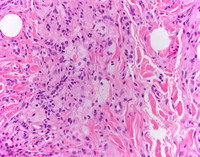

Low power H&E

Punch biopsy show diffuse dermal infltrate of bland cells with pale cytoplasm.

At higher power, foamy histocytes with bland nuclear morphology occurring singly and in aggregates are noted. These cells are characterized by vacuolated cytoplasm,  often in a fibrotic background with admixed chronic inflammation.